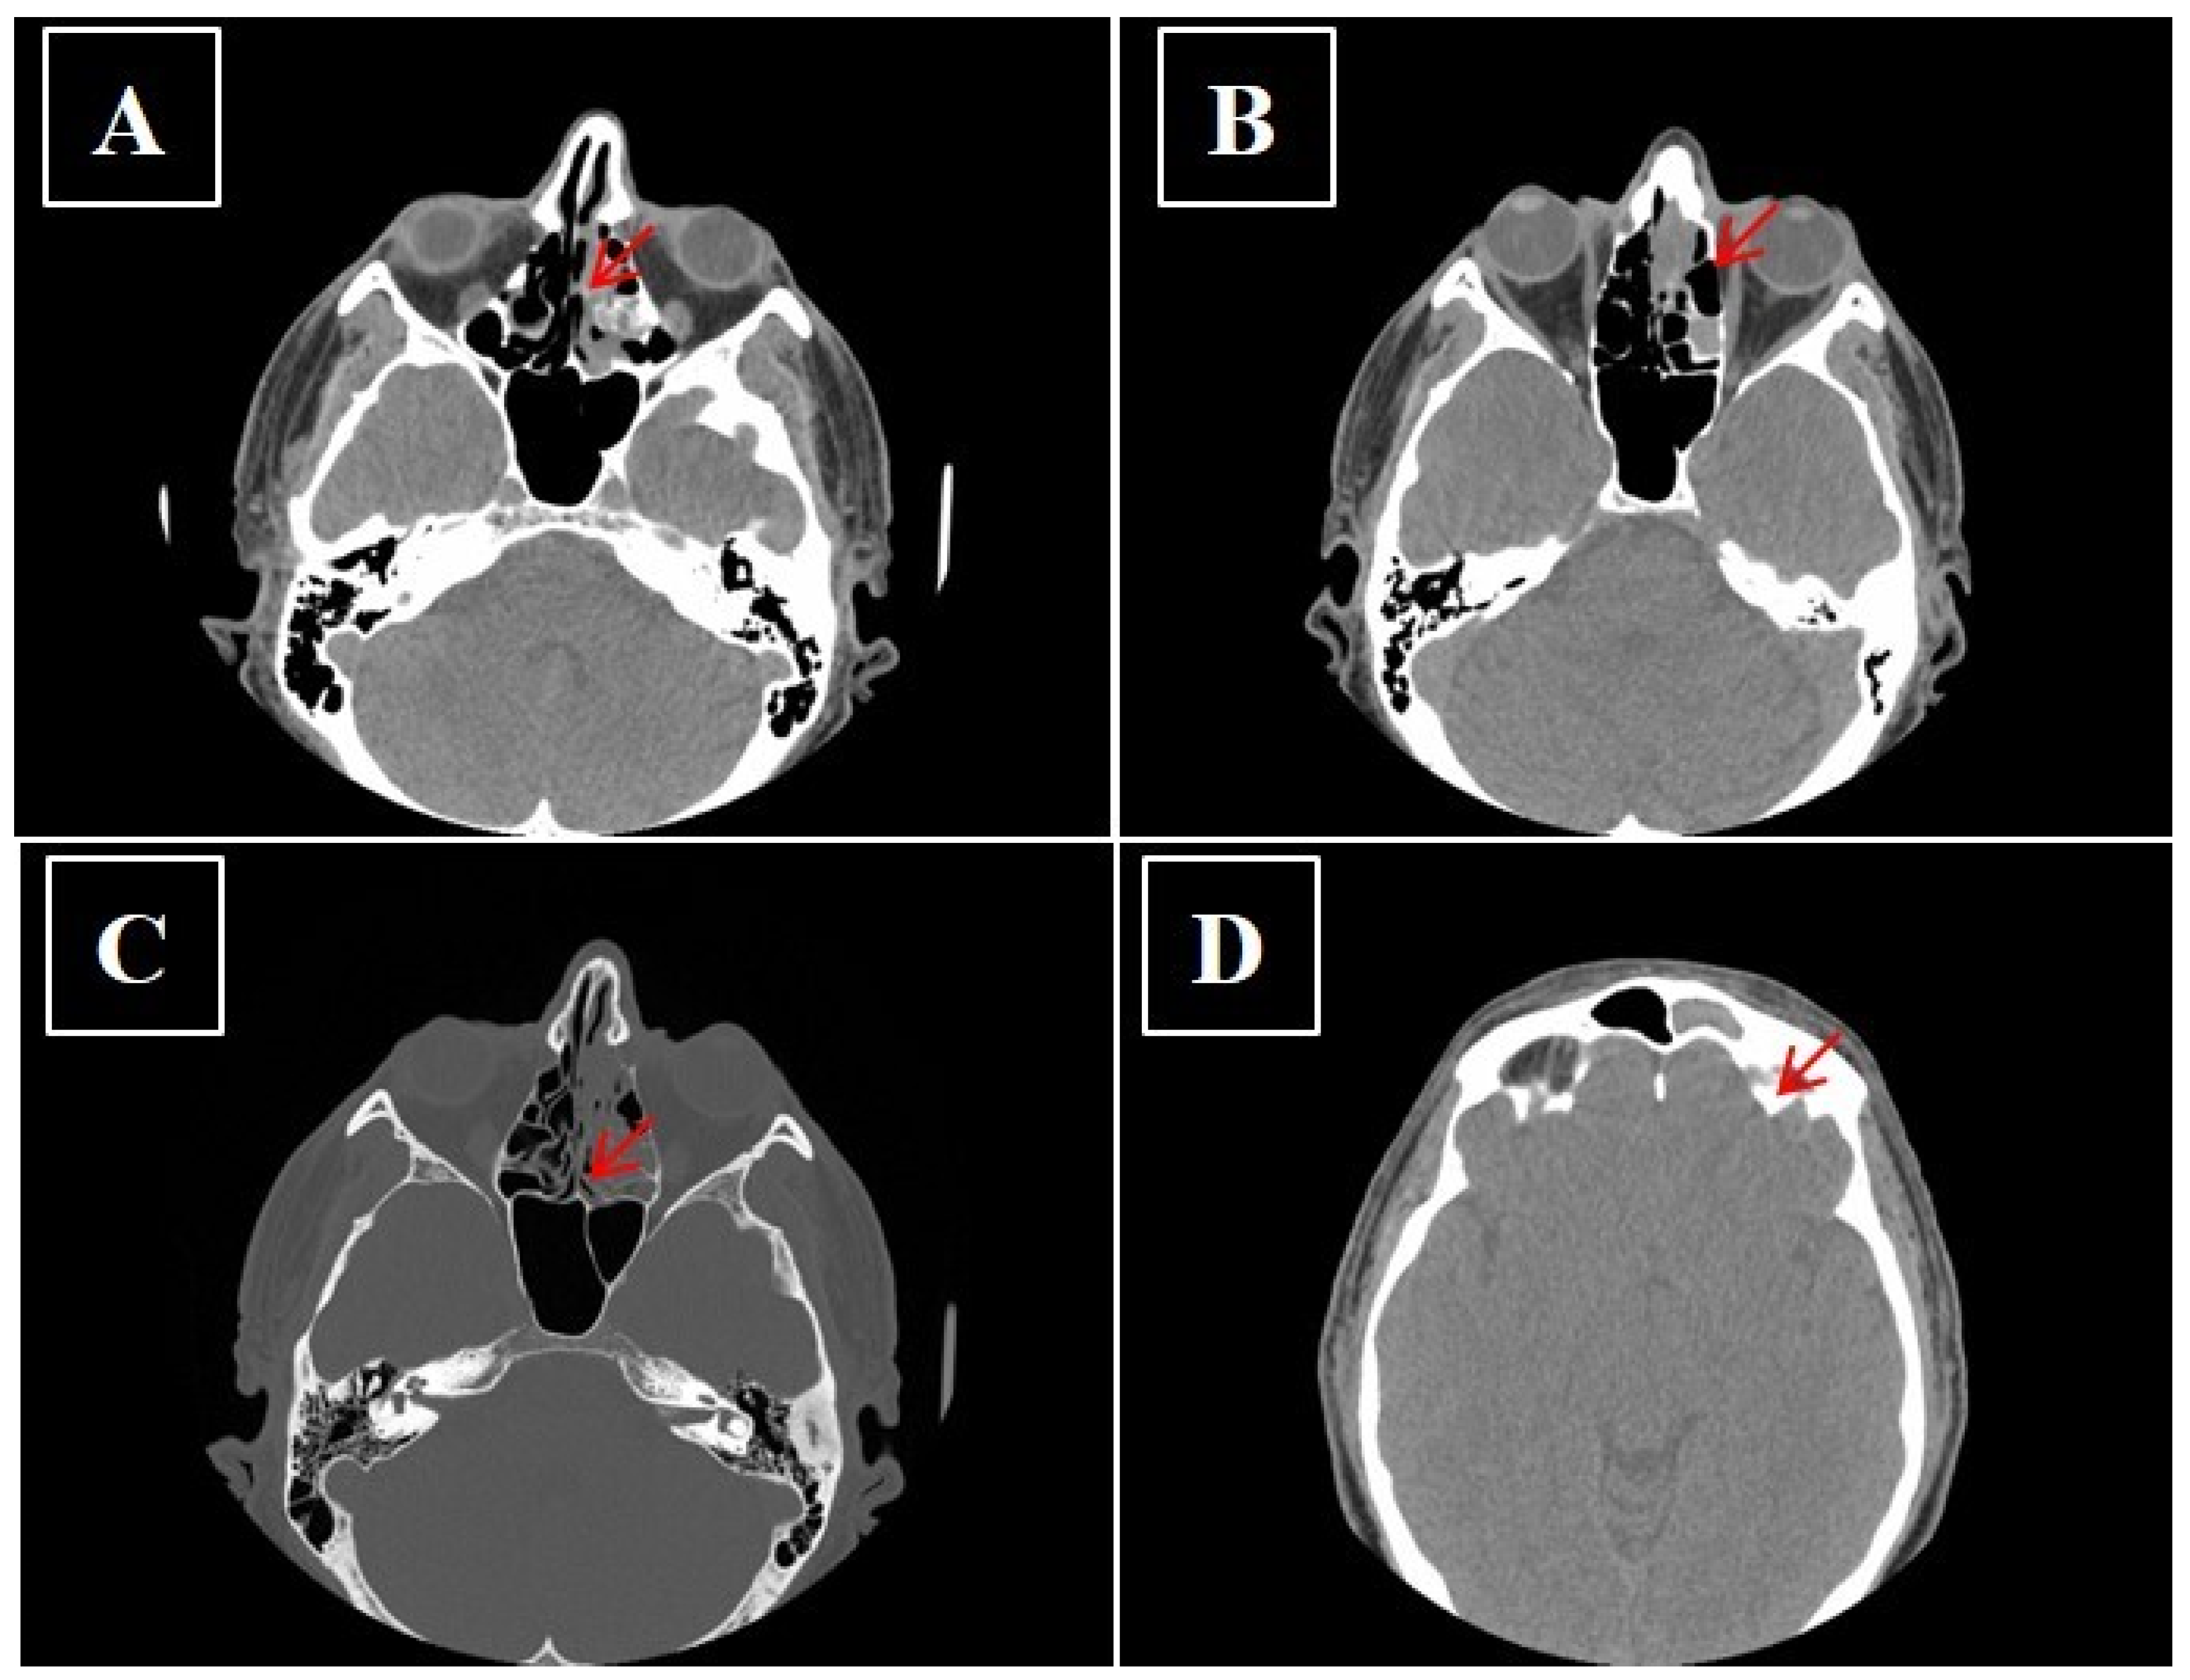

- Kawaguchi, M.; Kato, H.; Tomita, H.; Mizuta, K.; Aoki, M.; Hara, A.; Matsuo, M. Imaging Characteristics of Malignant Sinonasal Tumors. J. Clin. Med. 2017, 6, 116. [Google Scholar] [CrossRef]

- Sivalingam, J.; Sarawagi, R.; Raghuwanshi, S.; Yadav, P.K. Sinonasal Neoplasia – Clinicopathological Profile And Importance of Computed Tomography. J. Clin. Diagn. Res. 2015, 9, TC01–TC04. [Google Scholar] [CrossRef]